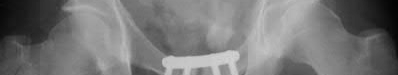

A 44-year-old male presents after being struck by a car. He is hypotensive, and has an obvious open tibia and a closed femoral shaft fracture. A pelvic radiograph is obtained and shown in Figure A. A representative CT scan image in shown in Figure B. The patient is placed in a pelvic binder, and his blood pressure normalizes with crystalloid and a blood transfusion. He then undergoes pelvic angiography, and his internal iliac artery is embolized. Which of the following definitive treatment options is most appropriate in this case?

The radiographs and CT scan show a fracture pattern consistent with an APC-III injury. This is most appropriately treated with pubic symphysis ORIF with a multi-hole plate and posterior iliosacral screw fixation.

APC-III pelvic ring injuries are associated with with disruption of the anterior and posterior SI ligaments (SI dislocation) as well as disruption of

sacrospinous and sacrotuberous ligaments. They are commonly associated with vascular injury and retroperitoneal bleeding.

Sagi et al studied the radiographic and clinical outcome of symphyseal plating techniques, specifically comparing two hole (THP) vs multi-hole plating (MHP). Retrospective review of charts and radiographs immediately after the index procedure to latest follow-up was performed. When comparing the 2 different methods of anterior fixation, they found that the rate of fixation failure was greater in group THP (33%) than group MHP (12%). When evaluating the presence of a malunion as a result of these 2 treatment methods, there were more present in the THP group (57%) than in the MHP group (15%). On the basis of these findings, the authors recommended multi-hole plating of unstable pubic symphyseal disruptions.

Grimshaw et al performed a biomechanical study to determine the failure risk and potential benefit to use of locked fixation constructs in simulated pelvic ring injuries. The authors used a six-hole 3.5-mm plate specifically designed for the symphysis pubis with the capability of fixation in locked or unlocked mode, six pelves were fixed with locked screws and six pelves were fixed standard unlocked bicortical screws. Biomechanical testing was performed, and no abrupt failures were noted. However, locked plating of the pubic symphysis did not appear to offer any advantage over the standard unlocked technique

Illustrations A, B, and C show the AP, outlet, and inlet postoperative radiographs.